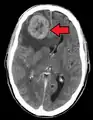

Diagnosis

Pulmonary metastases shown on Chest X-Ray

The cells in a metastatic tumor resemble those in the primary tumor. Once the cancerous tissue is examined under a microscope to determine the cell type, a doctor can usually tell whether that type of cell is normally found in the part of the body from which the tissue sample was taken.

For instance, breast cancer cells look the same whether they are found in the breast or have spread to another part of the body. So, if a tissue sample taken from a tumor in the lung contains cells that look like breast cells, the doctor determines that the lung tumor is a secondary tumor. Still, the determination of the primary tumor can often be very difficult, and the pathologist may have to use several adjuvant techniques, such as immunohistochemistry, FISH (fluorescent in situ hybridization), and others. Despite the use of techniques, in some cases the primary tumor remains unidentified.